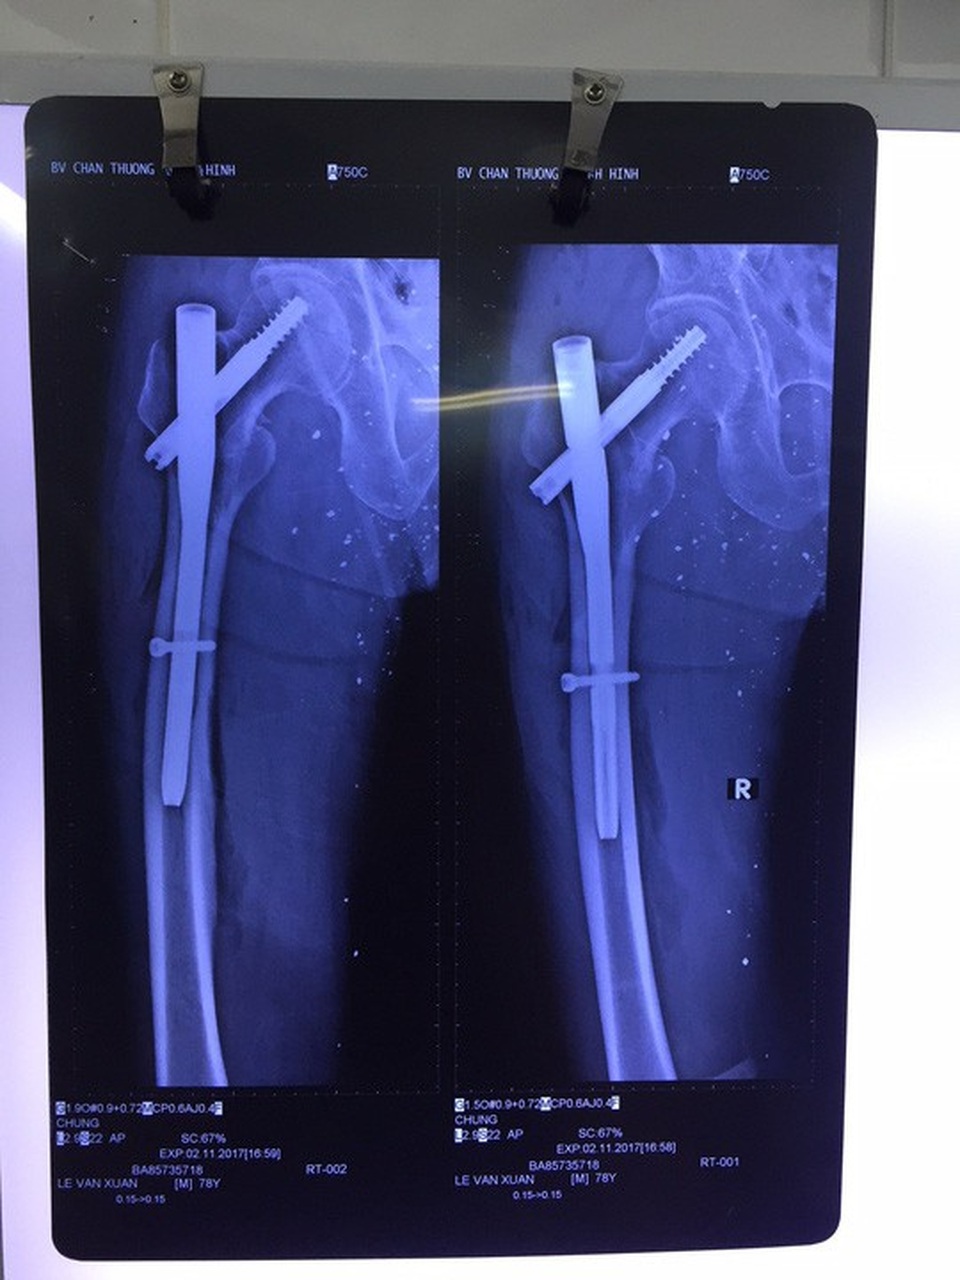

Ngày 27-11, Bệnh viện Chấn thương Chỉnh hình TP HCM cho biết vừa phẫu thuật bắt đinh vít bảo tồn thành công khớp háng cho một cụ ông bị trượt chân té tại nhà.

Qua hội chẩn, các bác sĩ xác định đây là 1 trường hợp gãy liên mấu chuyển có thể mổ bảo tồn, giữ lại khớp háng thật cho ông. Sau khi giải thích cho người nhà, ê kip phẫu thuật Khoa Chấn thương Chỉnh hình đã quyết định phẫu thuật chọn dụng cụ đinh kết hợp xương đầu gần xương đùi mới nhất để phẫu thuật cho ông.

Theo BS Nguyễn Huy Toàn, thành viên ê kíp phẫu thuật, ưu điểm của loại đinh này là đường mổ nhỏ (chỉ cần 3 vết rạch da dài 2-5 cm) không mở ổ gãy nên xương dễ lành, ít mất máu, ít đau hơn so với các phương pháp truyền thống. Ngoài ra, thiết kế loại đinh này rất vững chắc, ngay ngày hôm sau có thể cho phép bệnh nhân đi chống chân chịu lực. Với các ưu điểm này, giúp người bệnh có thể ngồi dậy sớm, ra khỏi giường bệnh, giảm áp lực chăm sóc lên người nhà.